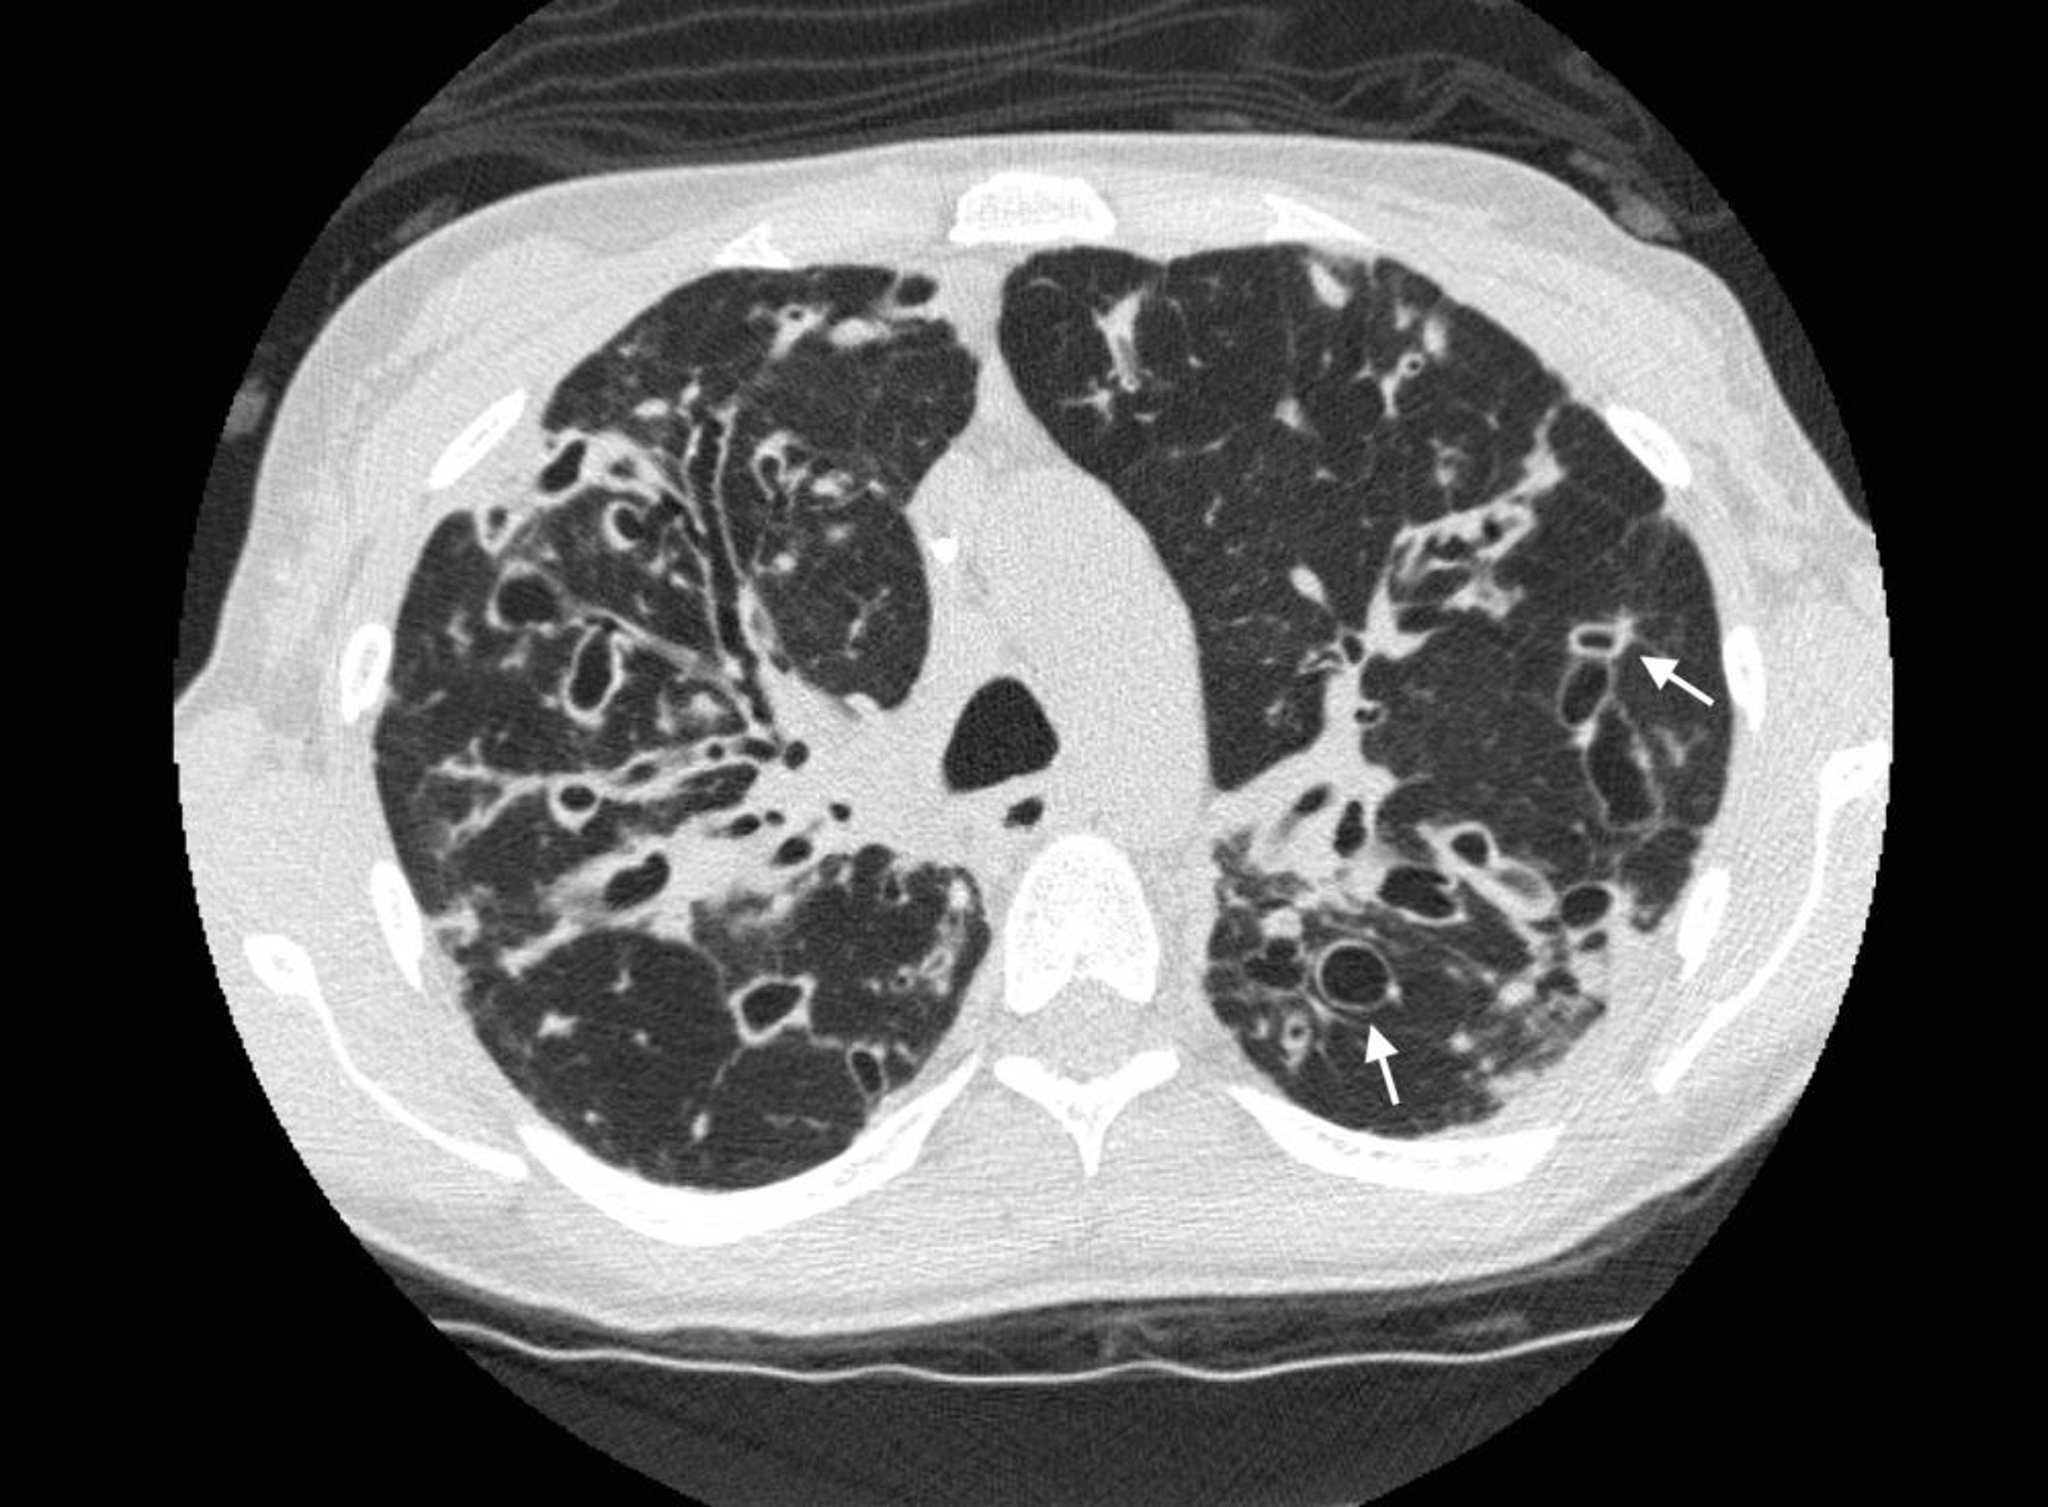

Bronchectasie (tomodensitométrie)

Une TDM du thorax chez un patient atteint de mucoviscidose montre une bronchectasie sévère dans les zones pulmonaires supérieures avec dilatation des voies respiratoires et anomalies kystiques. Les flèches montrent le signe de la chevalière, où une voie respiratoire dilatée (l'anneau) est adjacente à une artère plus petite (le sommet de l'anneau). Normalement, les voies respiratoires ont la même taille que les artères adjacentes ou sont plus petites que celles-ci.

Photo courtesy of Başak Çoruh, MD.